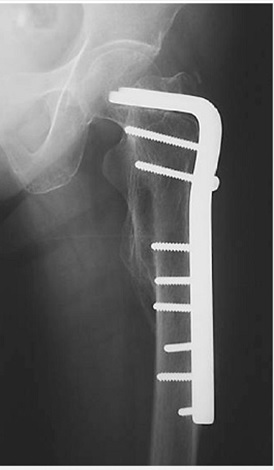

عكس و راديوگرافي نشانده پيچ ديناميك هيپ (DHS) براي فيكساسيون شكستگي اينترتروك است